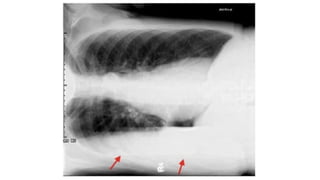

Hydro pneumothorax